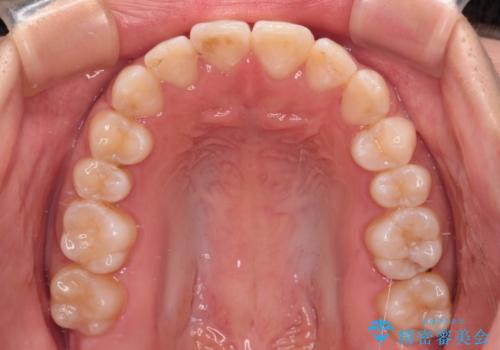

当初予定通り、1年で治療を終えることができました。

後戻り防止はマウスピースで行うため、急に自己管理が必要となるため、移動の最後をマウスピース矯正で行うことで、マウスピース非装着による後戻りリスクを回避する工夫をしています。